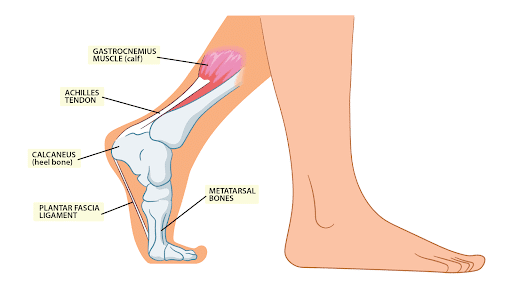

Product Name: Achilles tendon sharp stabbing pain new arrivals

The Signs of Achilles Tendinitis Sydney Heel Pain new arrivals, Heel Pain Causes Treatment and Prevention new arrivals, Sharp Pain in the Achilles Tendon Causes Best Treatment new arrivals, Achilles tendinitis Information Mount Sinai New York new arrivals, Achilles Tendonitis Treatment in Gilbert Scottsdale Chandler Mesa Phoenix new arrivals, Achilles Tendon Tear Kenneth Bramlett MD new arrivals, Know the Symptoms of Achilles Tendonitis Tendinopathy Gait Happens new arrivals, What Causes Pain In Back Of Heel Tendon Injury Symptoms new arrivals, Achilles Tendon Pain and Injury Treatment in Chatswood new arrivals, Achilles Tendon Pain Causes Treatment Sydney Heel Pain new arrivals, Achilles Tendinopathy Kintec Footwear Orthotics new arrivals, Fast Effective Relief for Achilles Tendon Pain Manchester Burnley new arrivals, Common Conditions Causing Heel Pain new arrivals, Insertional Achilles Tendinopathy Sussex Foot And Ankle Clinic new arrivals, Achilles Tendinitis Symptoms Treatment new arrivals, Achilles tendon sharp clearance pain new arrivals, Severs Disease Sever s Disease Treatment Sydney new arrivals, Sharp Pain in Foot Causes Symptoms and Treatments Modern Foot Ankle new arrivals, Achilles Tendonosis and Tendonitis Achilles Tendonosis and Tendonitis Chiropractors for Chandler Sun Lakes and Ocotillo Arizona new arrivals, Heel Pain Bunbury Foot Ankle Surgeon new arrivals, Achilles Tendon Pain Causes Treatments Prevention new arrivals, What Can Cause Sharp Stabbing Foot Pain new arrivals, Protecting Your Achilles Heel From Injury Dr Gordon Slater new arrivals, Pain In The Back Of The Heel What Could It Mean new arrivals, Plantar fasciitis Altru Health System new arrivals, Spink Physiotherapy Achilles tendon pain Achilles tendon pain often occurs due to overuse sudden increased intensity of physical activity poor footwear tight calf muscles improper warm up inadequate r... new arrivals, Pain at the back of the heel How to figure out what s causing it and what to do about it new arrivals, 4 Heel Pain Symptoms to Take Seriously Chicagoland Foot and Ankle Board Certified Foot and Ankle Specialists and Surgeons new arrivals, Sharp Pain in the Achilles Tendon Causes Best Treatment new arrivals, Ankle Pain Causes Treatment Northeast Spine and Sports Medicine new arrivals, Achilles Tendinitis Ankle Pain Foot Injury new arrivals, Achilles Tendonitis Causes Symptoms Signs Gleneagles Hospital new arrivals, Pain at the back of the heel How to figure out what s causing it and what to do about it new arrivals, Achilles Tendonitis Vs Plantar Fasciitis Which Do I Have new arrivals, Achilles Tendon Pain Symptoms Causes Treatment Exercises new arrivals.

Achilles tendon sharp stabbing pain new arrivals